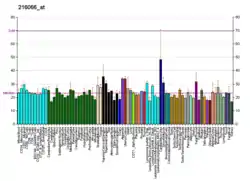

It was discovered that a mutation in the ABCA1 protein is responsible for causing Tangier disease by several groups in 1998. Gerd Schmitz's group in Germany[6] and Michael Hayden's group in British Columbia[7] were using standard genetics techniques and DNA from family pedigrees to locate the mutation. Richard Lawn's group at CV Therapeutics in Palo Alto, CA used cDNA microarrays, which were relatively new at the time, to assess gene expression profiles from cell lines created from normal and affected individuals.[8] They showed cell lines from patients with Tangier's disease showed differential regulation of the ABCA1 gene. Subsequent sequencing of the gene identified the mutations. This group received an award from the American Heart Association for their discovery.[9] Tangier disease has been identified in nearly 100 patients worldwide, and patients have a broad range of biochemical and clinical phenotypes as over 100 different mutations have been identified in ABCA1 resulting in the disease.[10]

ABCA1 mediates the efflux of cholesterol and phospholipids to lipid-poor apolipoproteins (apoA1 and apoE) (reverse cholesterol transport), which then form nascent high-density lipoproteins (HDL). It also mediates the transport of lipids between Golgi and cell membrane. Since this protein is needed throughout the body it is expressed ubiquitously as a 220 kDa protein. It is present in higher quantities in tissues that shuttle or are involved in the turnover of lipids such as the liver, the small intestine and adipose tissue.[13]

Mutations in this gene have been associated with Tangier disease and familial high-density lipoprotein deficiency. ABCA1 has been shown to be reduced in Tangier disease which features physiological deficiencies of HDL.[22][23] Leukocytes ABCA1 gene expression is upregulated in postmenopausal women receiving hormone replacement therapy (HRP).[24] ABCA1 expression is also upregulated in tumor-associated astroctytes surrounding glioblastoma brain tumors, and is important to the tumor progression. [25][26]